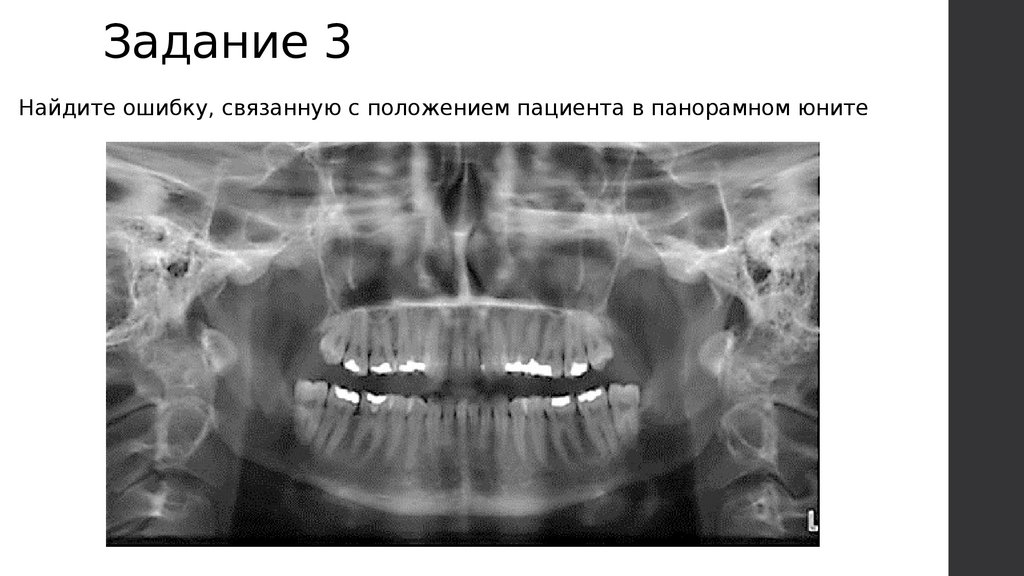

Задание 3

Найдите ошибку, связанную с положением пациента в панорамном юните